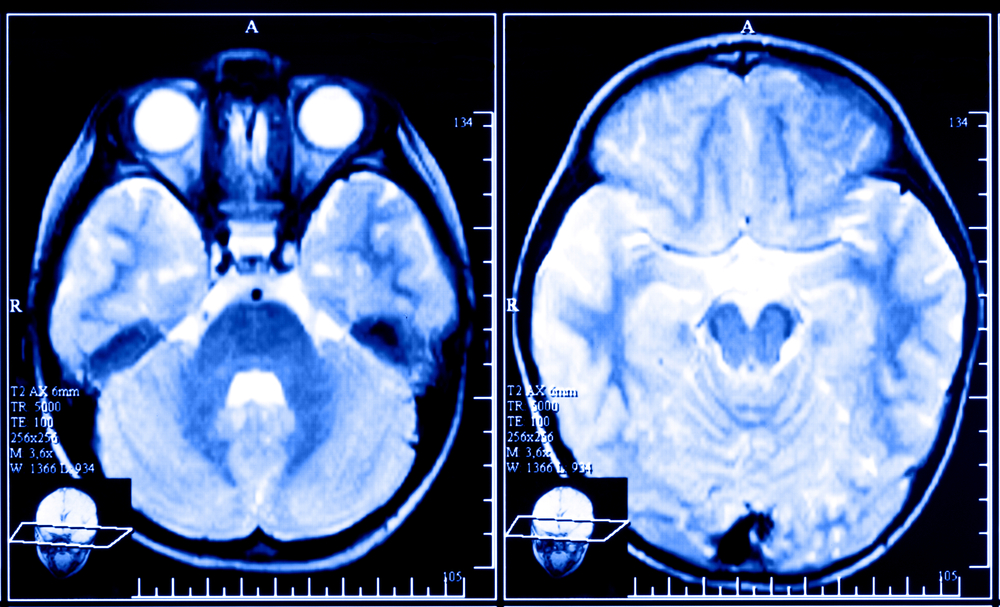

It’s possible to create brain patterns associated with affection and tenderness, using neurofeedback while someone is scanned in a functional magnetic resonance (fMRI) machine. The latest research has taken place in Brazil. “While lying in an fMRI machine, subjects were asked to think of memories of affection and pride while viewing a screen with a circle. The researchers used pattern-detection algorithms called ‘support vector machines’ to classify patterns in the participants’ brains. When these patterns were detected, the circle would ripple and change shape. (It didn’t change for the control group.)”